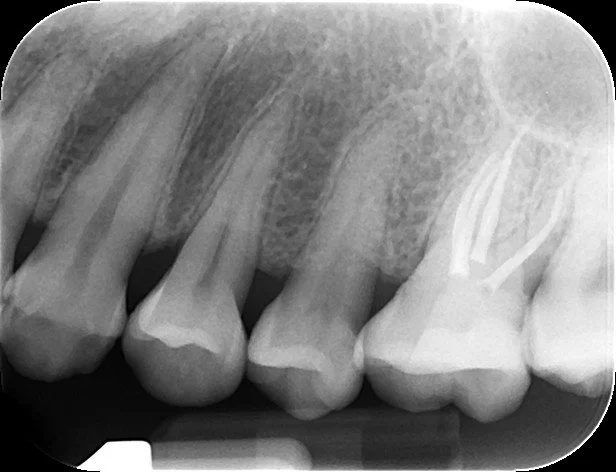

Fixed pros

Dental Implants

Endodontics